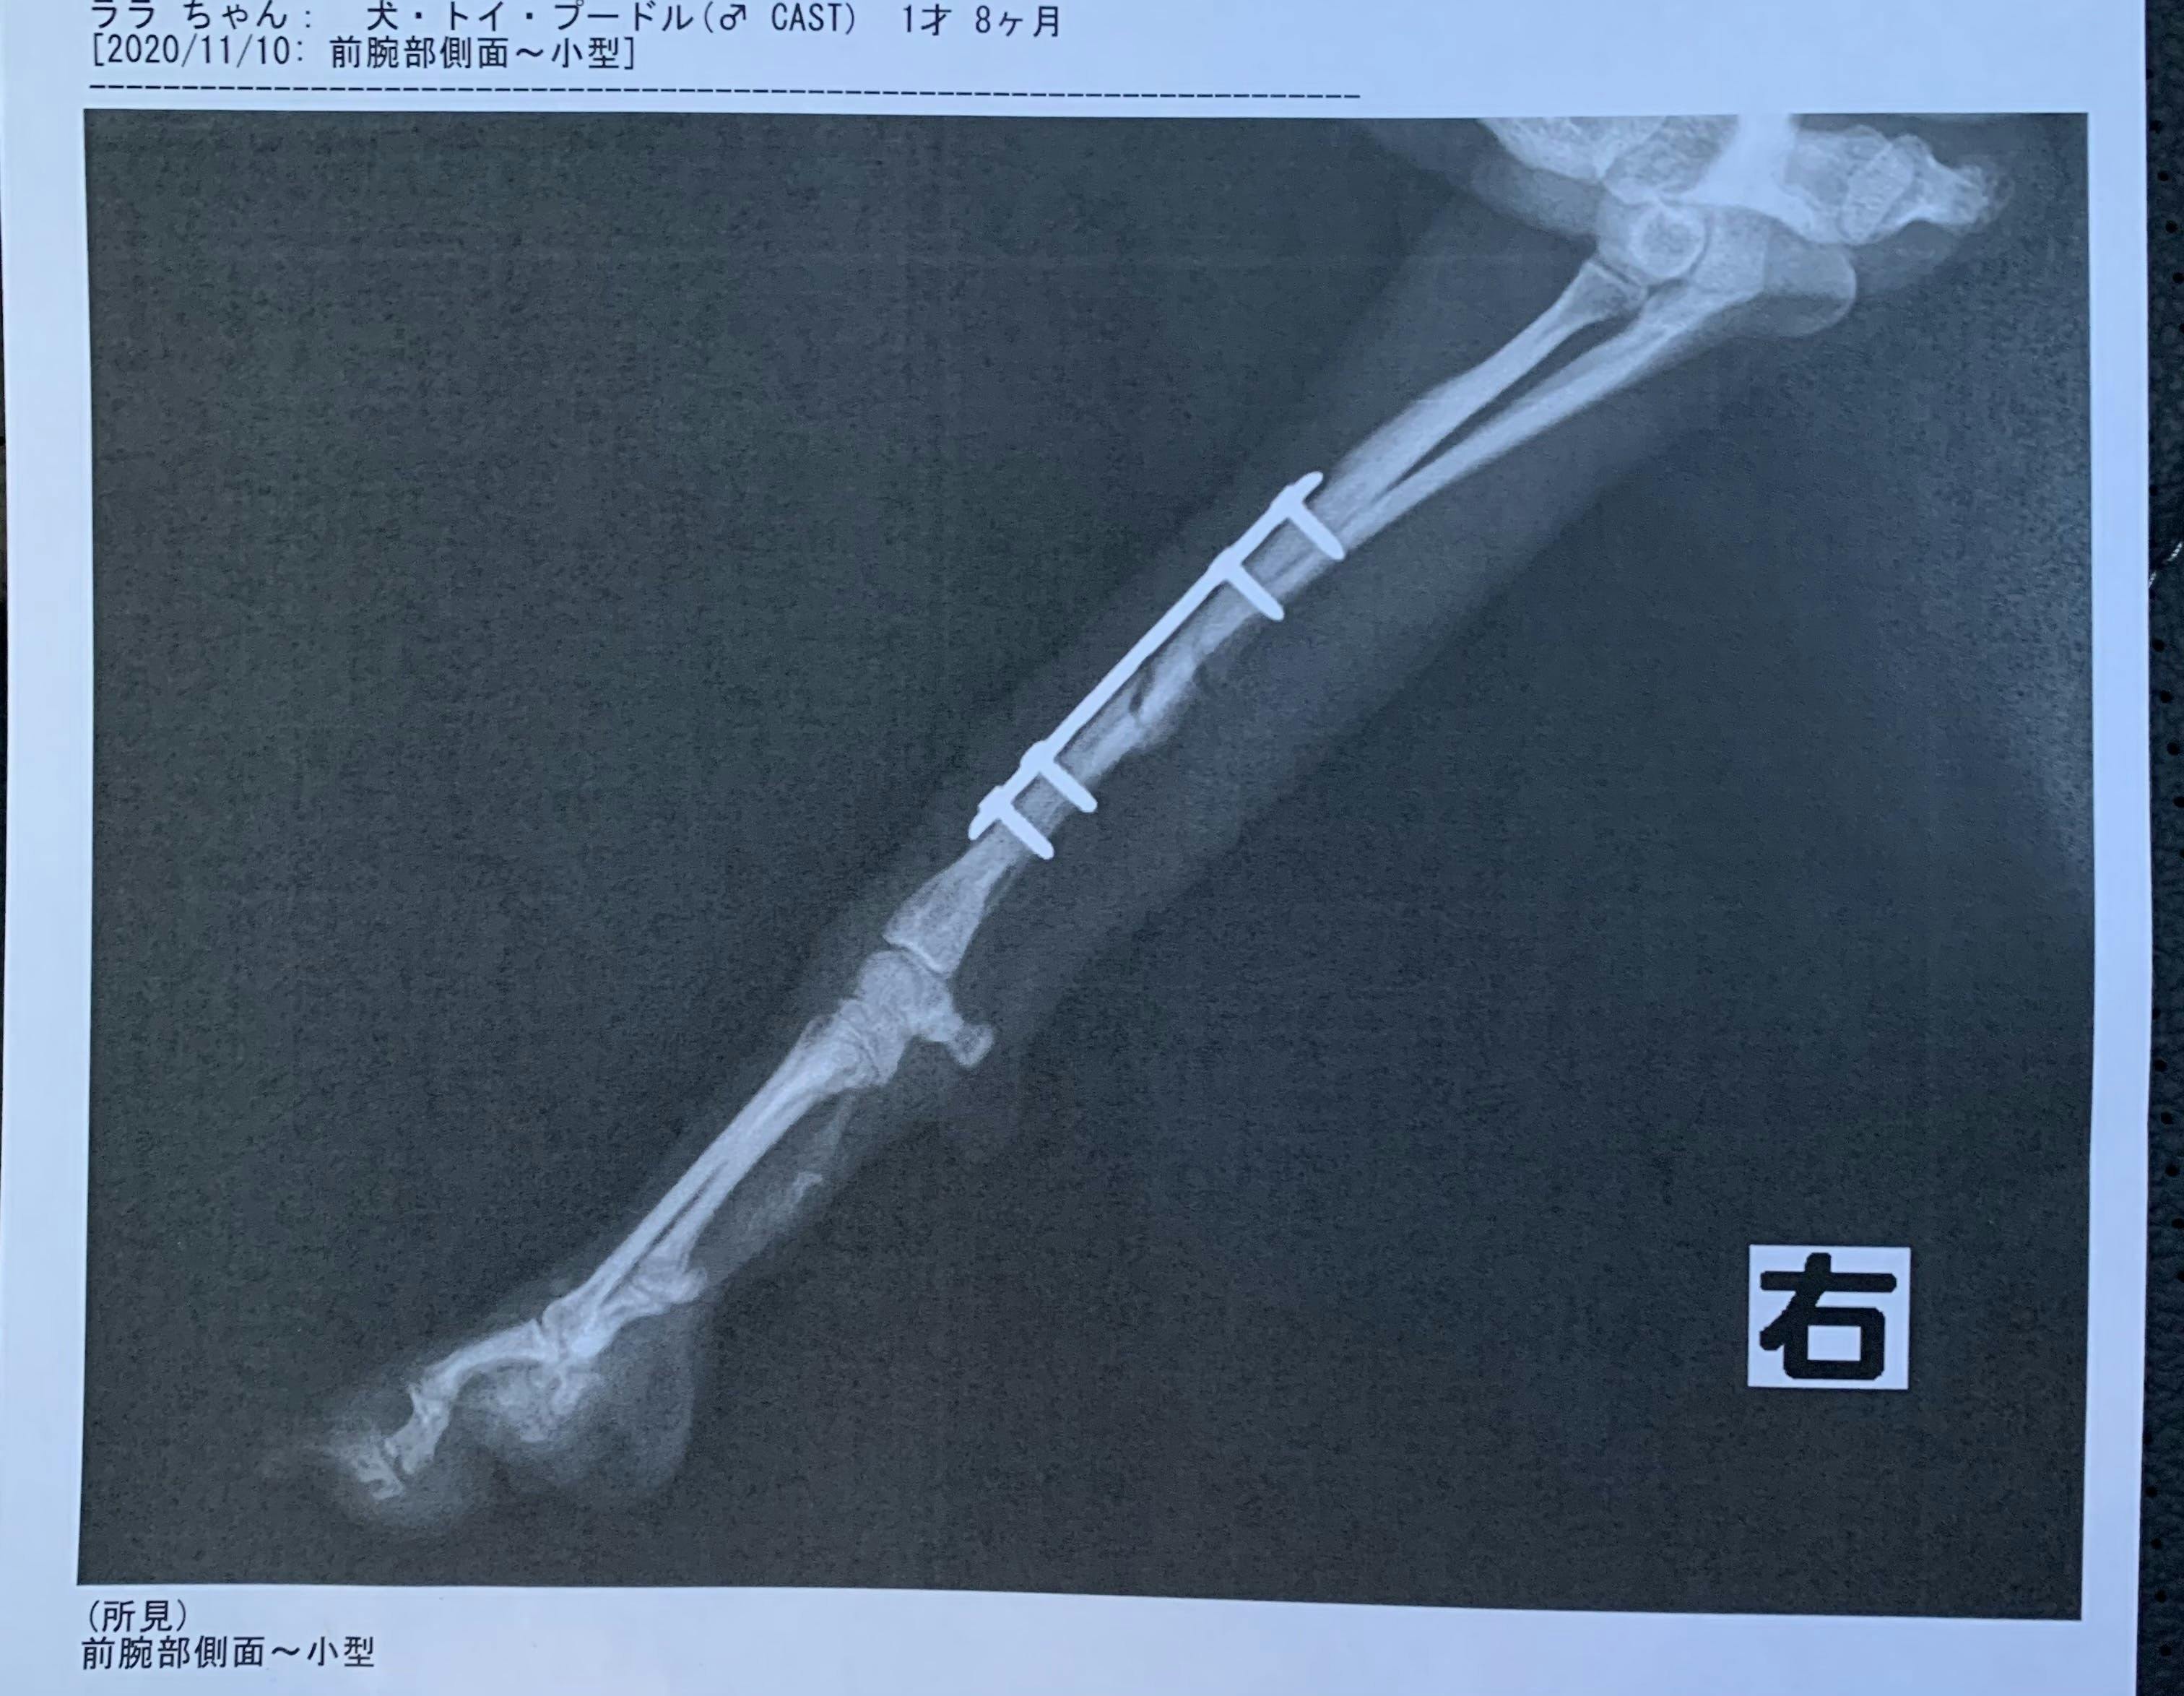

現在愛犬ララは骨折してからボルドを4本入れ入院しています。どうか皆様のご協力いただけませんでしょうか。

現在ボルドを右足に4本入れて固定していて、12月〜来年の1月に骨が治っていれば2つのボルドを取り除く手術をします。状況を見て完治していれば残りの2つのボルドを取り除く手術をします。

実際にボルドでとめている写真です。